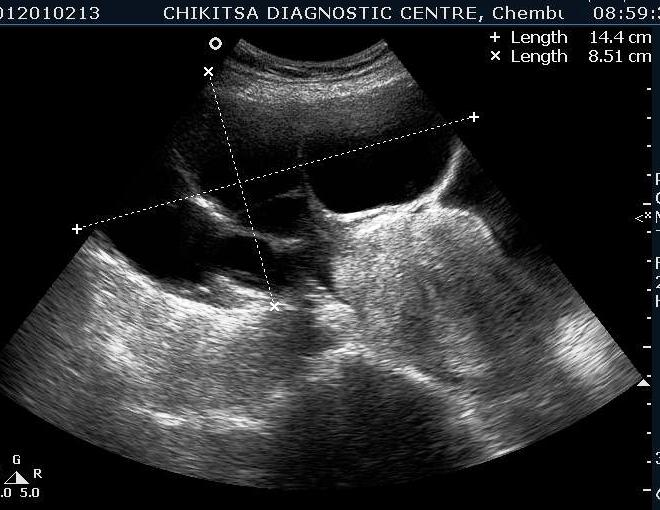

A 35 year old female was referred to our centre by a gynaecologist with gradually increasing distension abdomen & discomfort ,with pressure downwards. She had two alive children , both delivered normally & one early abortion , now tubectomised for 5 years.She had normal regular periods with cycle 3-5/25-35 days. No history of dysmenorrhoea.No history of any chronic medical illness. On ultrasound abdominally, one large mass of 15 cm x 10 cm with multiple septations was seen. On colour flow, vascularity was noted in the septal walls. No papillary projections seen in the mass.No solid areas seen in the mass.Uterus & right ovary were found to be normal. Diagnosis of left benign ovarian tumour ? mucinous cystadenoma was made which was confirmed on HPE after left ovariotomy .

Multiple thin septae are present and low levels echoes due to mucoid material present in the dependant portions of the mass. In mucinous Cystadenomas, individual locules may vary in imaging appearance due to difference in degree of hemorrhage and protein content. That's the differentiating point between serous and mucinous. Smooth inner wall structures are more reliable characteristics in predicting benignity. Presence of solid components and lesion without measurable wall thickness and demonstrable inner wall structure suggested malignancy. The difference in chemical components and difference in viscosity is responsible for sonographic echogenicity.

Identification of papillary projections on an imaging study is important because they are the single best predictor of the epithelial character of a neoplasm and may correlate with the aggressiveness of the tumor.

Absence of ascitis favoured benign lesions and its presence meant more chances of the lesion being malignant.